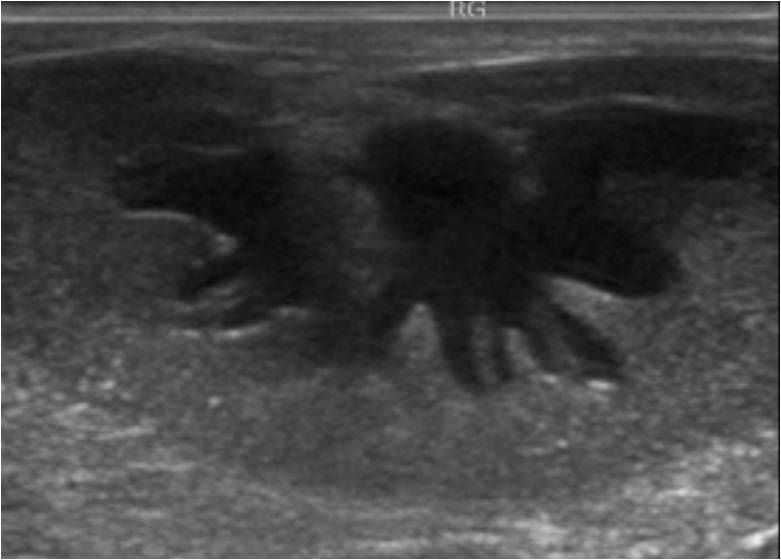

Maladie digestive du furet

Les furets sont très sujets aux maladies digestives. Leurs selles peuvent être de consistance plus ou moins moulées mais parfois on notera des diarrhées régulières. C'est ce que l'on appelle les maladies digestives chroniques du furet. Il existe de très nombreuses causes à cela, elles peuvent être d'origine alimentaire, inflammatoire, tumorale (lymphome), parasitaire ou encore bactérienne (hélicobacter). Le diagnostic se fait principalement par prise de sang, échographie et par endoscopie digestive. Cette dernière permet de faire des prélèvements pour confirmer le diagnostic et ajuster le traitement. La maladie digestive peut s'étendre au foie.

Helicobacter : une bactérie fréquente dans l'estomac des furets